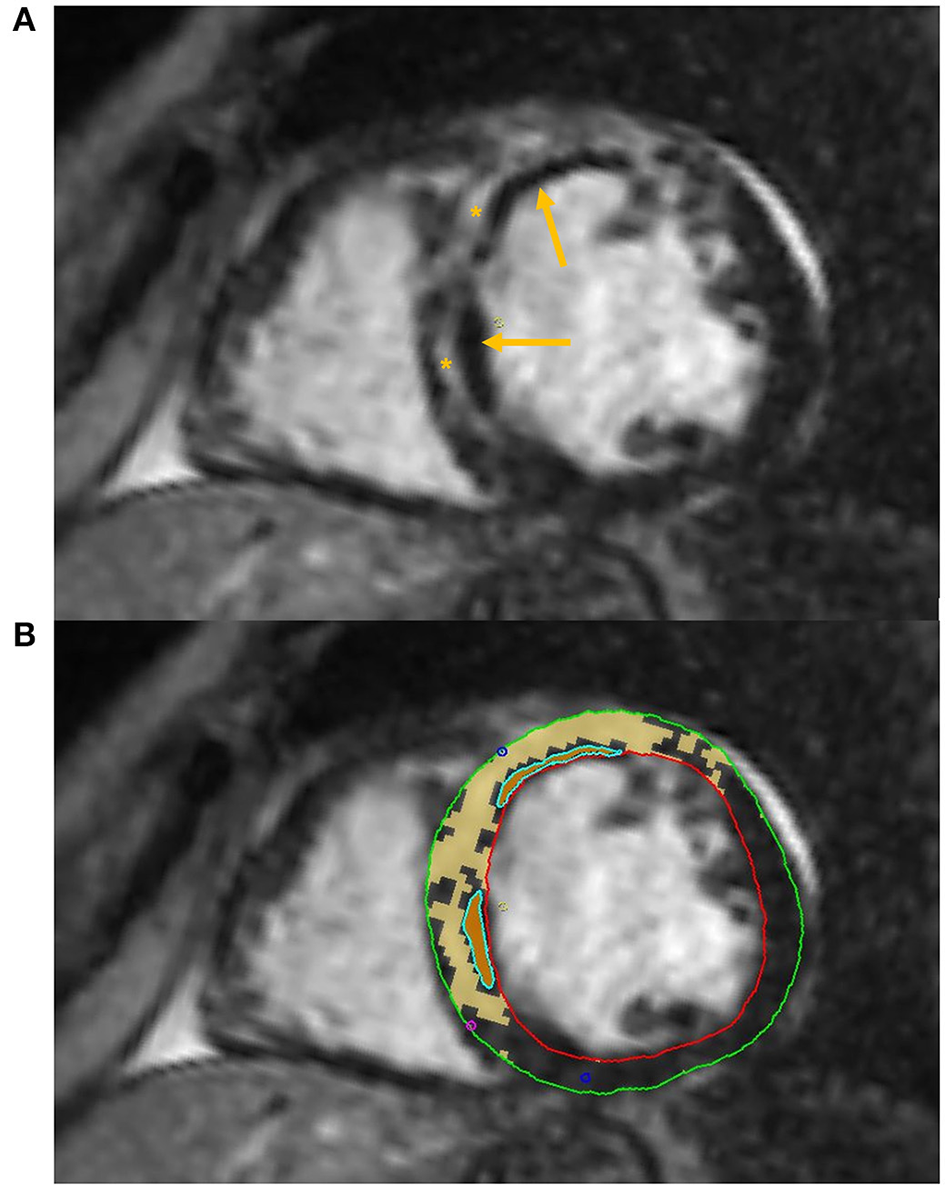

Some authors have successfully applied DL algorithms to perform automated LGE quantification (Figure 3).

Figure 3

Tissue characterization with Cardiac Magnetic Resonance (CMR). The figure shows an example of tissue characterization in a patient with a history of antero-septal myocardial infarction. (A) Depicts a transmural myocardial scar (asterisks) in the antero-septal region with concomitant evidence of subendocardial areas of microvascular obstruction (MVO, arrows). (B) Shows the automatic identification and quantification of late gadolinium enhancement and the semi-automatic identification of MVO areas on CMR images.

A recent study by Ma et al. (45) has also proven the ability of texture analysis combined with native T1 mapping values to better identify microvascular obstruction (MVO, Figure 3) compared to T1 mapping alone in a small group of patients with recent ST-segment-elevation MI. Combined radiomics features and native T1 values also provided a higher predictive value for LV longitudinal systolic myocardial contractility recovery compared to T1 values in a subset of patients that underwent 6-months follow up CMR.